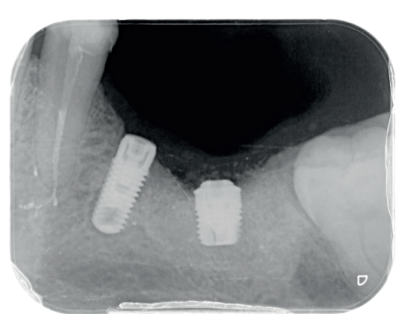

Al quinto mes se realizó un CBCT de control, para evaluar la homogeneidad en la zona y se planificó la colocación de un implante corto de 5 x 6 mm de Proclinic® (Figura 9) al mismo tiempo que fue tomada una biopsia de la zona. Se procedió a inyectar la misma anestesia que en la primera cirugía, se elevó un colgajo a espesor total y se tomó una biopsia con trefina de 3.5 mm de la zona injertada (Figura 10). En la misma zona donde fue realizada la toma de biopsia, sin pasar ninguna otra fresa, se colocó el implante empleándolo como expansor, de modo que se condensasen las paredes que rodeaban al implante (Figura 11).

En la revisión realizada a los seis meses, el paciente ha recuperado la función y la estética y está plenamente satisfecho con el resultado (Figura 14.) La radiografía periapical de control de los implantes cargados presenta buenos niveles óseos y una completa integración del injerto de dentina (Figura 15).